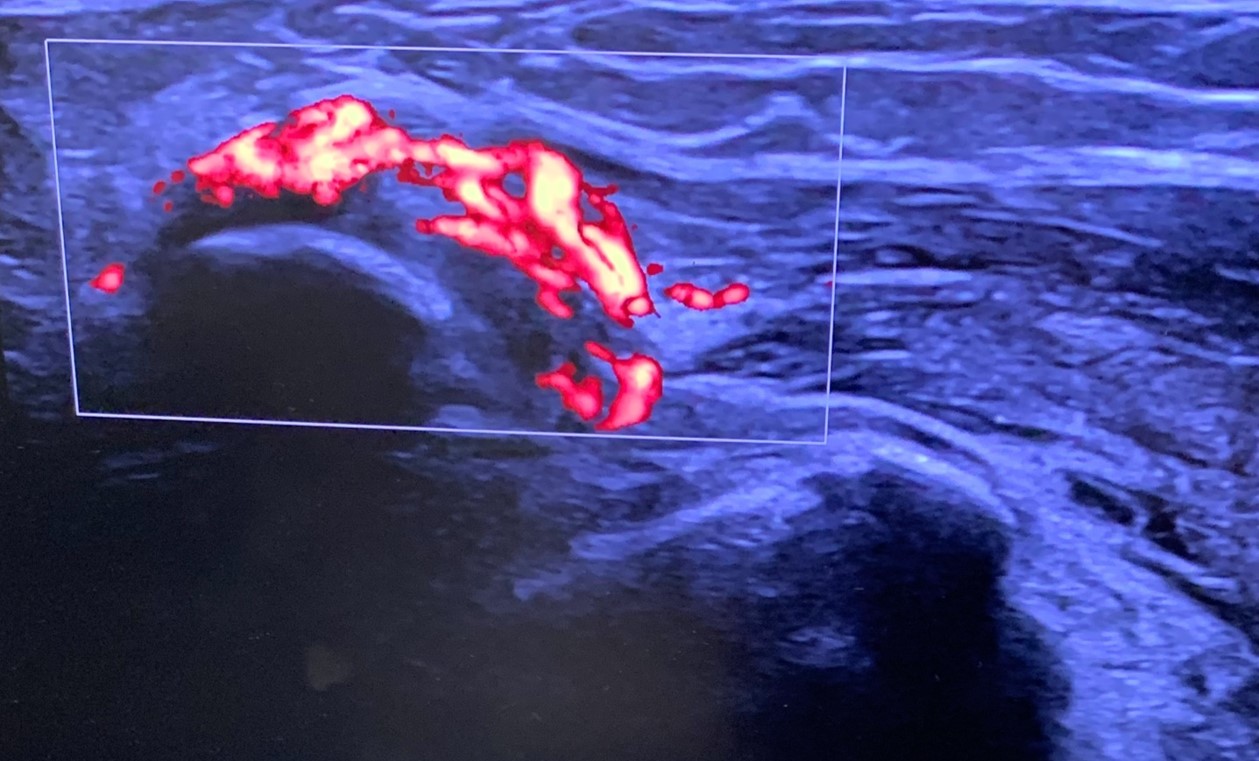

On the dorsum of the foot, ultrasound demonstrated marked cortical irregularity and callus formation around the third metatarsal shaft accounting for the palpable ‘lump’ with surrounding soft tissue swelling (Figure 1). On power Doppler, there was marked peripheral vascularity in the surrounding soft tissues (Figure 2). Incidentally, there was also cortical irregularity and callus formation around the second metatarsal shaft although the patient was not particularly tender here whilst scanning (Figure 3). The cortical irregularity in the second metatarsal shaft was minimal when compared to the third metatarsal and there was no neovascularisation on power Doppler indicating this was an older/mature injury.

Ultrasound appearances in keeping with acute and chronic stress fractures. A radiograph confirmed old and new callus formation (Figure 4). Conservative treatment comprised rest and analgesia. Surgery is generally reserved for stress fractures that do not heal.